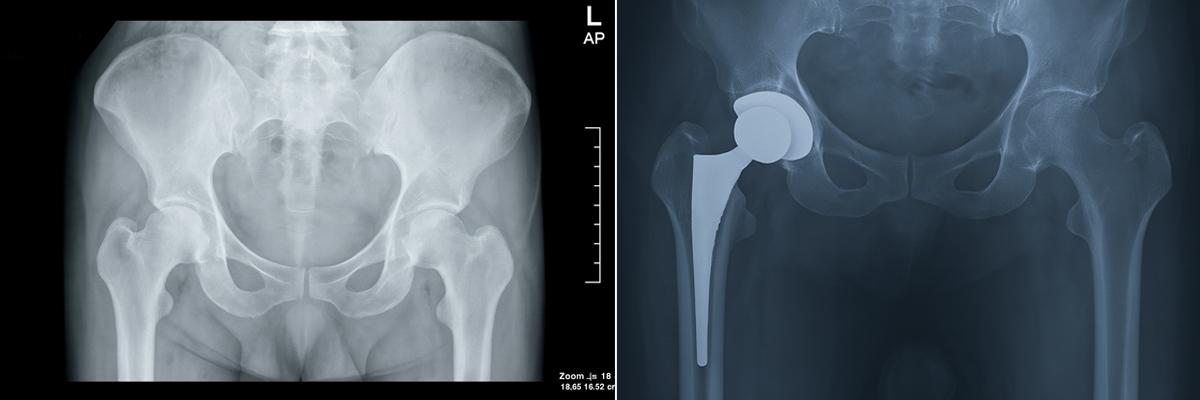

1. Resurfacing the Damaged Hip Joint

Primary Hip Replacement involves removing the worn-out cartilage and resurfacing the hip joint with high-quality metal, ceramic, or polyethylene implants, helping restore smooth joint function and relieve chronic pain.

4. Advanced Bearing Surface Materials

The bearing surfaces used in hip implants include polyethylene, ceramic, and metal, selected based on durability, friction reduction, and compatibility with the body.

5. Cemented, Uncemented & Hybrid Fixation Options

Hip implants can be fixed using uncemented (press-fit), cemented, or hybrid fixation techniques, depending on the Patient’s age, bone quality, and local joint condition.